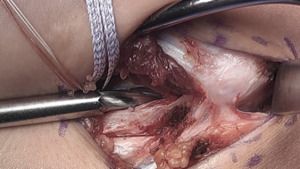

Proximal Drill Holes

At the base of the medial epicondyle, with caretaken to lateralize the proximal tunnel, a 2.5 mm drill bit is used to make a starter hole for the larger drill bit to follow.

This initial hole is then over drilled with either a 4.0- or 4.5-mm drill bit to a depth of 15 to 17 mm.

A 2.5 mm drill bit is is used to create two divergent tunnels through the proximal cortex of the medial epicondyle. Utilizing a Hewson suture passer, doubled over 2-0 vicryl sutures are passed.

One arm of the tendon graft is docked, with a #2 ortho cord suture with a baseball stitch with one arm of the internal brace. The second arm of the tendon graft is cut to an appropriate length, and the second #2 Ortho cord suture is placed. The second arm of the tendon graft is then docked proximally, followed by the second arm of the internal brace.

The internal brace suture arms are first tensioned and tied using a knot tier. Five throws are placed in the suture arms. The tendon graft sutures are then tensioned and tied as well. *Note that the internal brace is tensioned and tied first to preset the tension on the joint. (Figure 17)